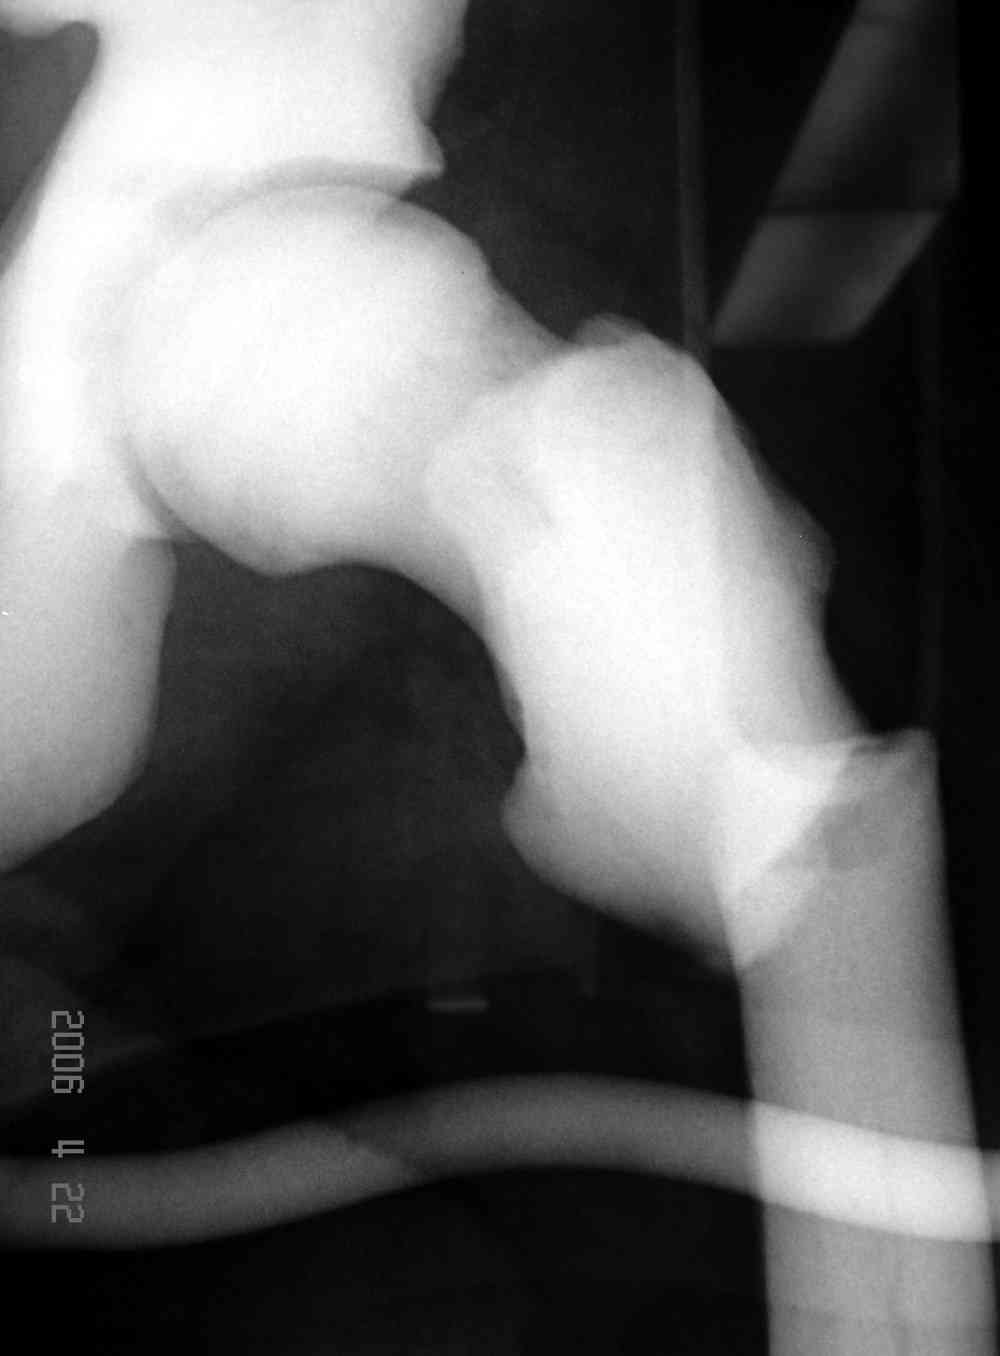

Представленные Вами данные о пациенте 57 дет с болезнью Альбертс-Шенберга чрезвычайно интересны, но диагноз вызывает большие сомнения. Для мраморной болезни характерно прееобладание склероза, а на представленных рентгенограммах преобладает симметричная дезорганизация архитектоники губчатой кости в эпиметафизарной зоне дистальных отделов бедер и голеней.

Мне кажется, представленные рентгенограммы скорее соответствуют варианту фиброзной дисплазии который был описан М. Campanacci (1976) или

Уважаемый Константин Иванович! Полностью согласен с проф. Михайловым, данный случай не похож на мраморную болезнь, при которой имеется резкое, строго симметричное и генерализованное уплотнение костной ткани (остеопетроз), и кость оказывается построенной преимущественно из гомогенного компактного костного вещества. Для примера привожу случай из архива нашего института (бедренные, плечевые кости и таз, рис 1,2,3)

Изменения структуры костей у Вашего пациента больше похожи на полиоссальную форму фиброзной дисплазии или болезнь Педжета, возможены также инфаркты костного мозга б.берцовых костей. К сожалению, качество снимка не очень хорошее, непонятно, сохранен ли кортикальный слой б.берцовых костей по передней поверхности.

Для примера привожу случай из архива американской ассоциации рентгенологов (ACR) - развитие злокачественной фиброзной гистиоцитомы на левой б.берцовой кости у пациента с множественными инфарктами костного мозга (рис 4,5 - левая, рис 6 - правая)